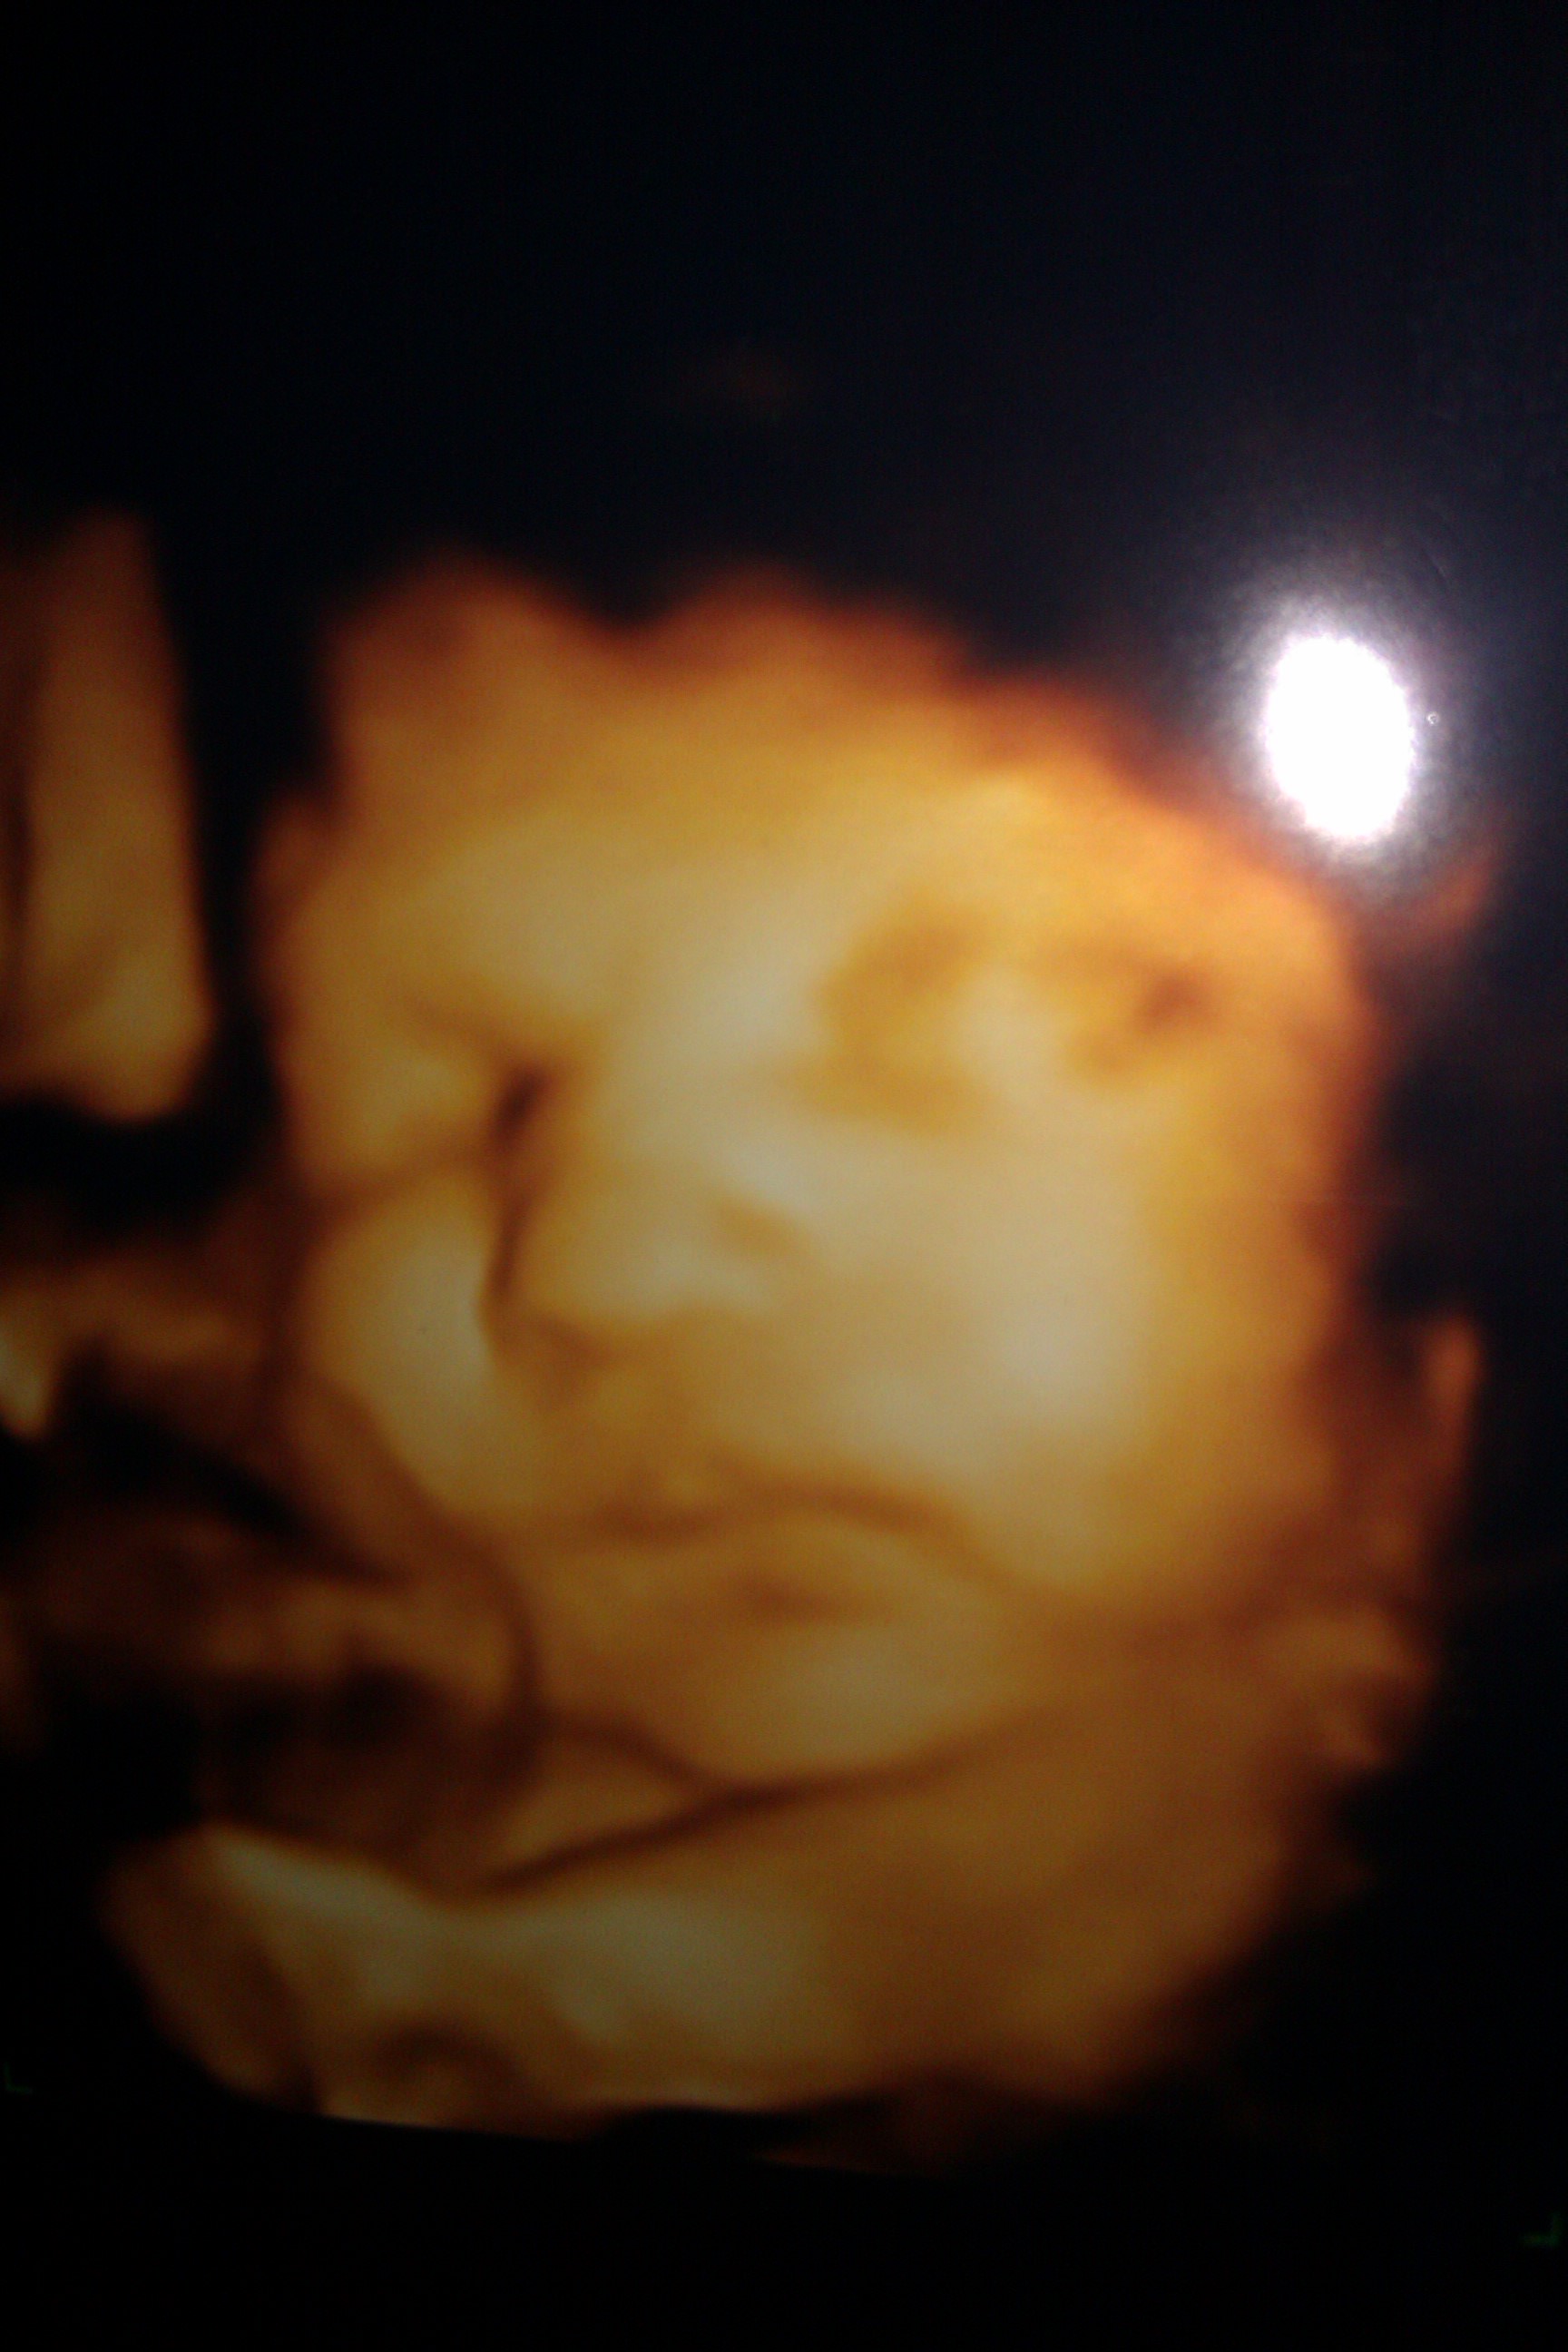

So they say its easier to pip on mobile now...here goes nothing. Here's a pic of my rainbow baby at 30 weeks. She will be here in 2 more weeks! Feel free to share your us Aww pics here.